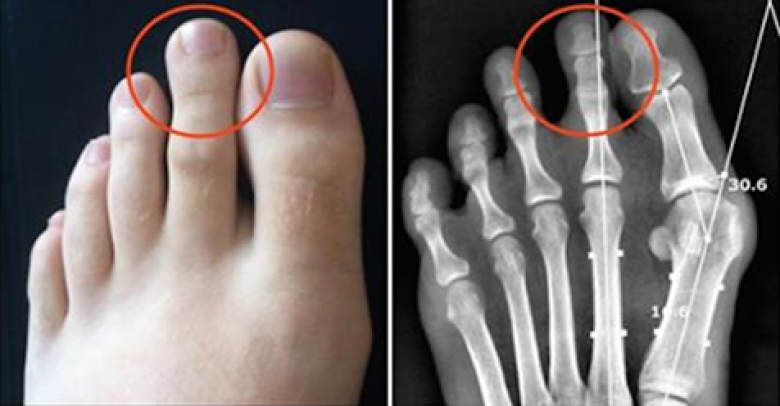

LifestyleВ Индии и Китае долгое время люди учились считывать определенные данные с ног, как бы это странно ни звучало. Некоторые верят, что через ноги можно познать характер человека. Например, если у Вас торчит косточка, значит, Вы часто сталкиваетесь с проблемами. Более того, ум и тело неразрывно связаны, и это может случить признаком отклонений. Давайте посмотрим, что могут сказать ноги о характере!